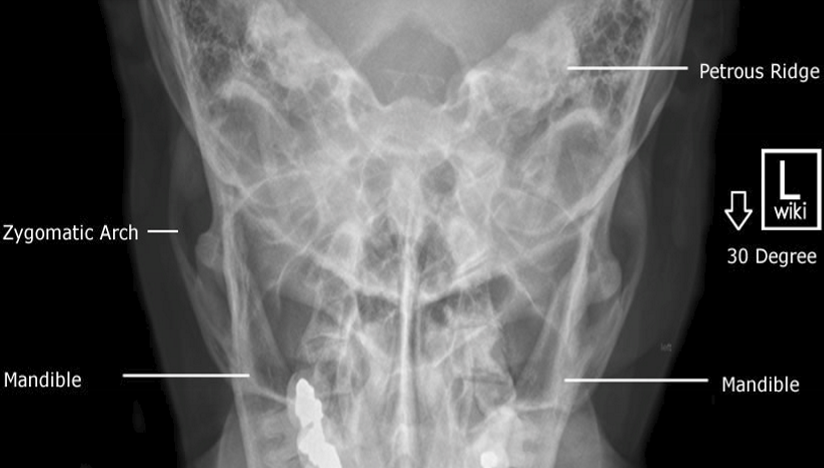

Please label